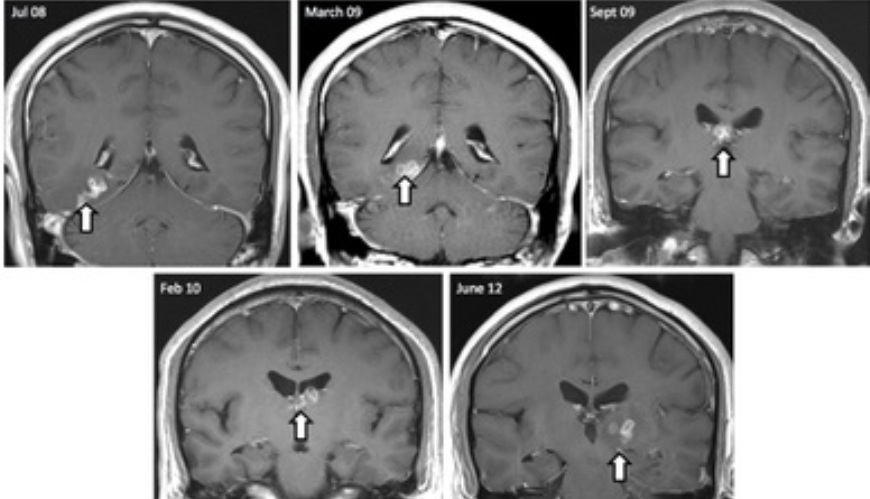

A través de una resonancia magnética se pudo determinar que su cerebro tenía una serie de lesiones. Sin embargo, los médicos desconocían las causas.

Pero durante los siguientes cuatro años se logró ver que las lesiones se desplazaron unos cinco centímetros del hemisferio izquierdo al derecho.

Después de numerosas pruebas y biopsas finalmente, en el año 2012, los médicos encontraron los restos de un gusano de unos 10 centímetros en el cerebro del hombre, quien fue tratado con medicina anti parasítica.